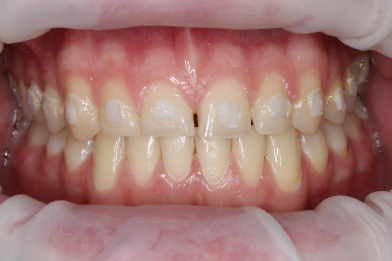

Реставрация верхних резцов с закрытием диастемы

Евсеенкова Дарья Эдуардовна -